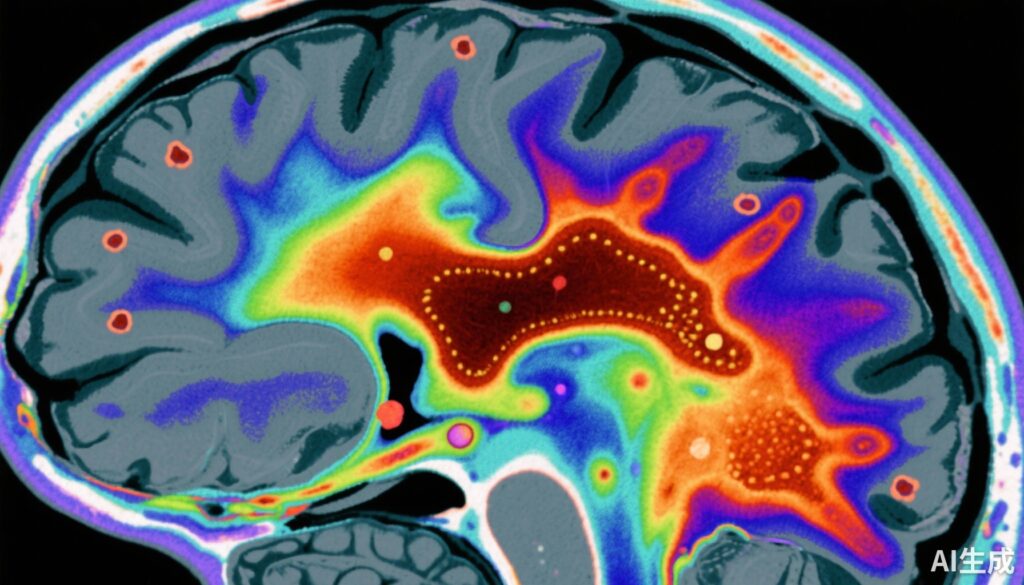

This case-control study conducted by Vano et al. included 159 participants: 79 patients with early-course schizophrenia (including antipsychotic-naïve or antipsychotic-free individuals) and 80 healthy controls. Quantitative susceptibility mapping (QSM) MRI was utilized to quantify magnetic susceptibility—a proxy for brain iron—in the substantia nigra and ventral tegmental area (SN-VTA).

The study found a statistically significant reduction in magnetic susceptibility in the SN-VTA region in schizophrenia patients compared to controls, with an effect size (Cohen’s d) of -0.66 (95% CI, -0.98 to -0.34). This suggests lower brain iron concentration in this critical midbrain dopaminergic region.

Correlation analysis demonstrated a significant inverse relationship (r = -0.44) between SN-VTA magnetic susceptibility and striatal dopamine synthesis capacity (Ki cer) assessed by PET. Thus, individuals with lower brain iron exhibited higher dopamine synthesis in the striatum, supporting the hypothesis that brain iron deficiency may promote hyperdopaminergia.

Regional analysis indicated the ventral SN-VTA exhibited the strongest associations, highlighting this subregion’s particular relevance to dopamine dysregulation in schizophrenia.